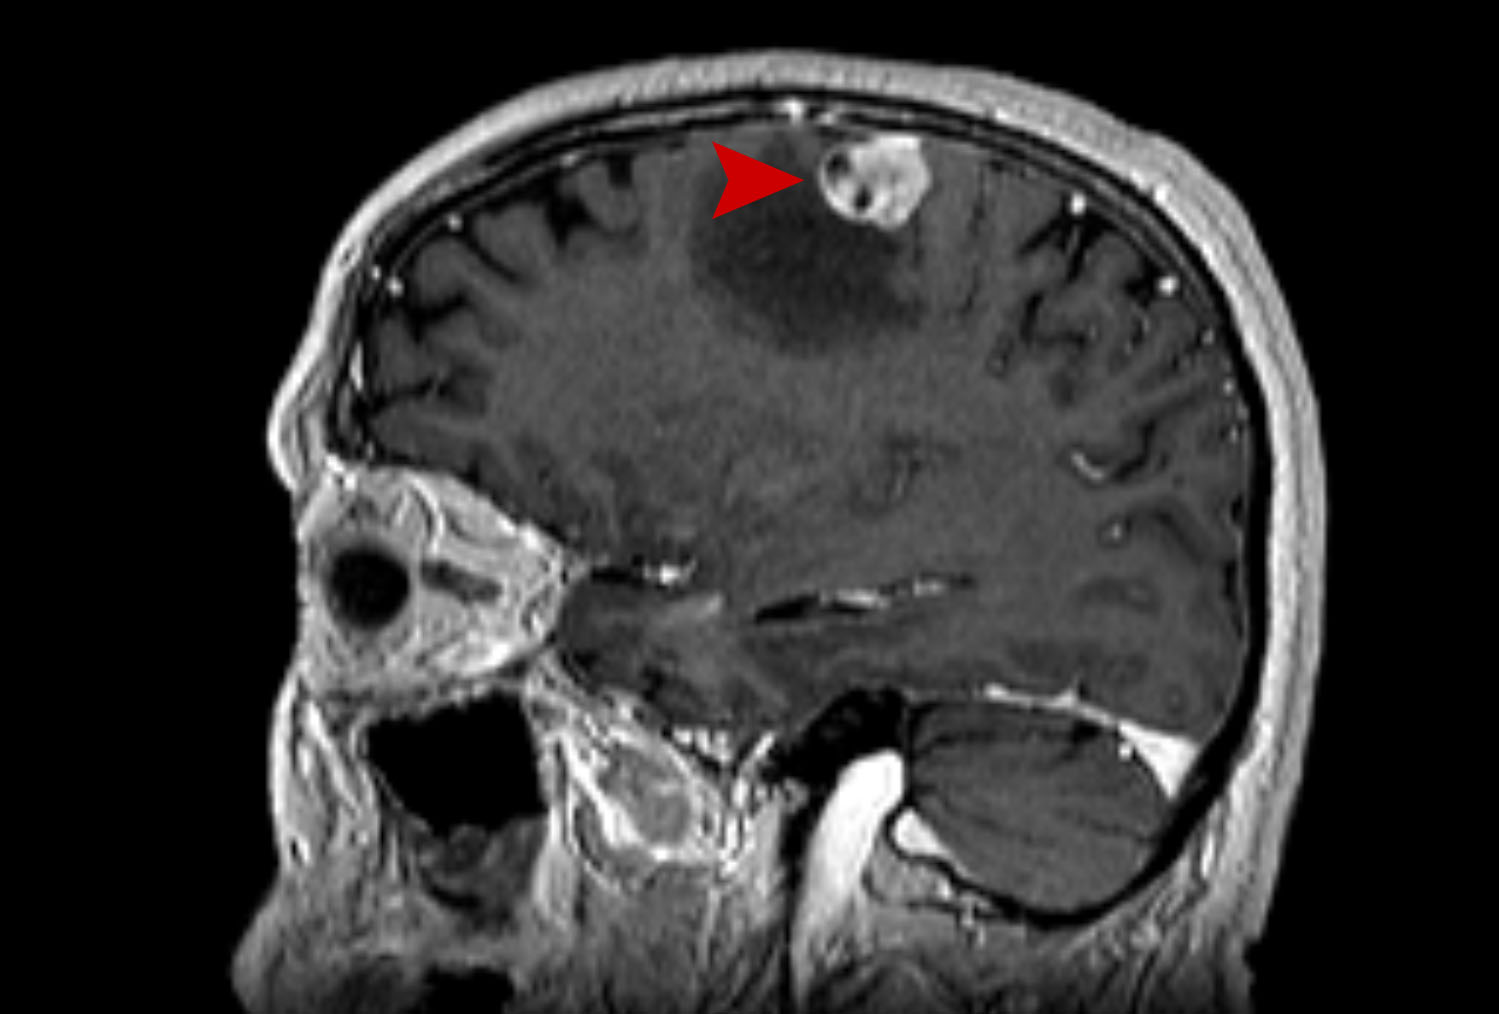

Μετάσταση στον Εγκέφαλο Θεραπεία με CyberKnife #31

Άρρεν 65 ετών με δευτεροπαθή εγκεφαλική εντόπιση αριστερά μετωπιαία από Ca παχέως εντέρου με συνοδό…